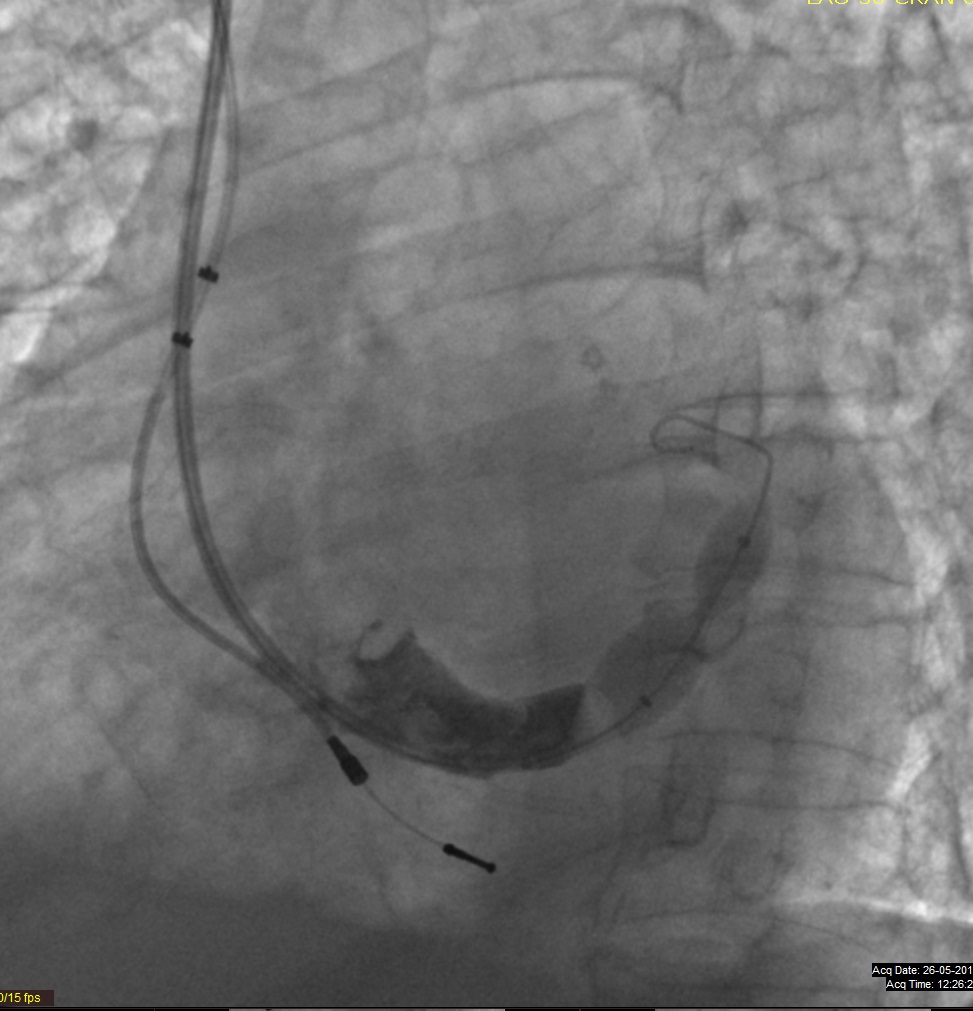

Imagem do dispositivo aplicado no paciente: /userfiles/images/reducer.jpg

O dispositivo é implantado através de uma veia do pescoço, apenas com anestesia local, e conduzido até à aurícula direita e seio coronário onde é expandido com um balão. O “Reducer” provoca aí um estreitamento focal que, aumentando a pressão no seio coronário, provoca uma redistribuição do sangue das áreas bem irrigadas do músculo cardíaco para as mal irrigadas, zonas que estão em isquemia e que produzem a dor cardíaca típica, a angina de peito.

O dispositivo é uma rede metálica em forma de ampulheta, expansível por balão, e foi desenvolvido para aliviar os doentes que não têm outras opções para atenuar ou eliminar a isquemia de causa cardíaca, também conhecida como angina de peito.